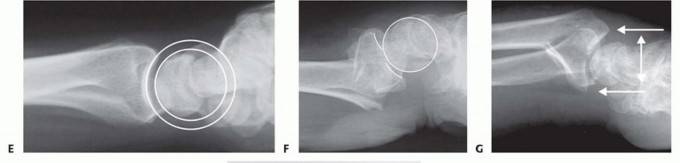

FIG 3 • Pathogenesis of dorsal radius fractures. A. Dorsal bending. B. Volar bending. C. Dorsal shear. D. Volar shear. E. Radial shear. F. Three-part articular. G. Comminuted articular. H. Carpal avulsion. I. High energy.

FIG 4 • A. Positioning for standard lateral radiography. B. Standard lateral radiograph. C. Positioning for 10-degree lateral radiography. D. Ten-degree lateral radiograph. Note the improved visualization of the articular surface of the base of the scaphoid facet and the entire lunate facet. Injuries from a high-energy mechanism present as complex comminuted fractures of the articular surface with extension into the radial/ulnar shaft ( FIG 3I).